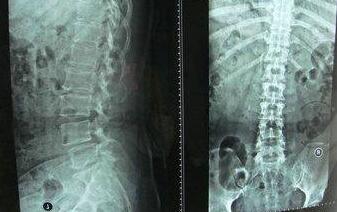

检查:实验室检查:HLA—B27阳性,ESR36mm/h,RF(-)。骶髂关节CT片示:符合骶髂关节炎(II级)改变。

(图:王先生入院时检查骶髂关节改变)

诊断:强直性脊柱炎。

(图:复诊时王先生骶髂关节恢复正常)

经过一个疗程的治疗,王先生强直的不适症状在消失;

连续三个疗程的治疗后,复查显示强直性脊柱炎已达临床 标准。